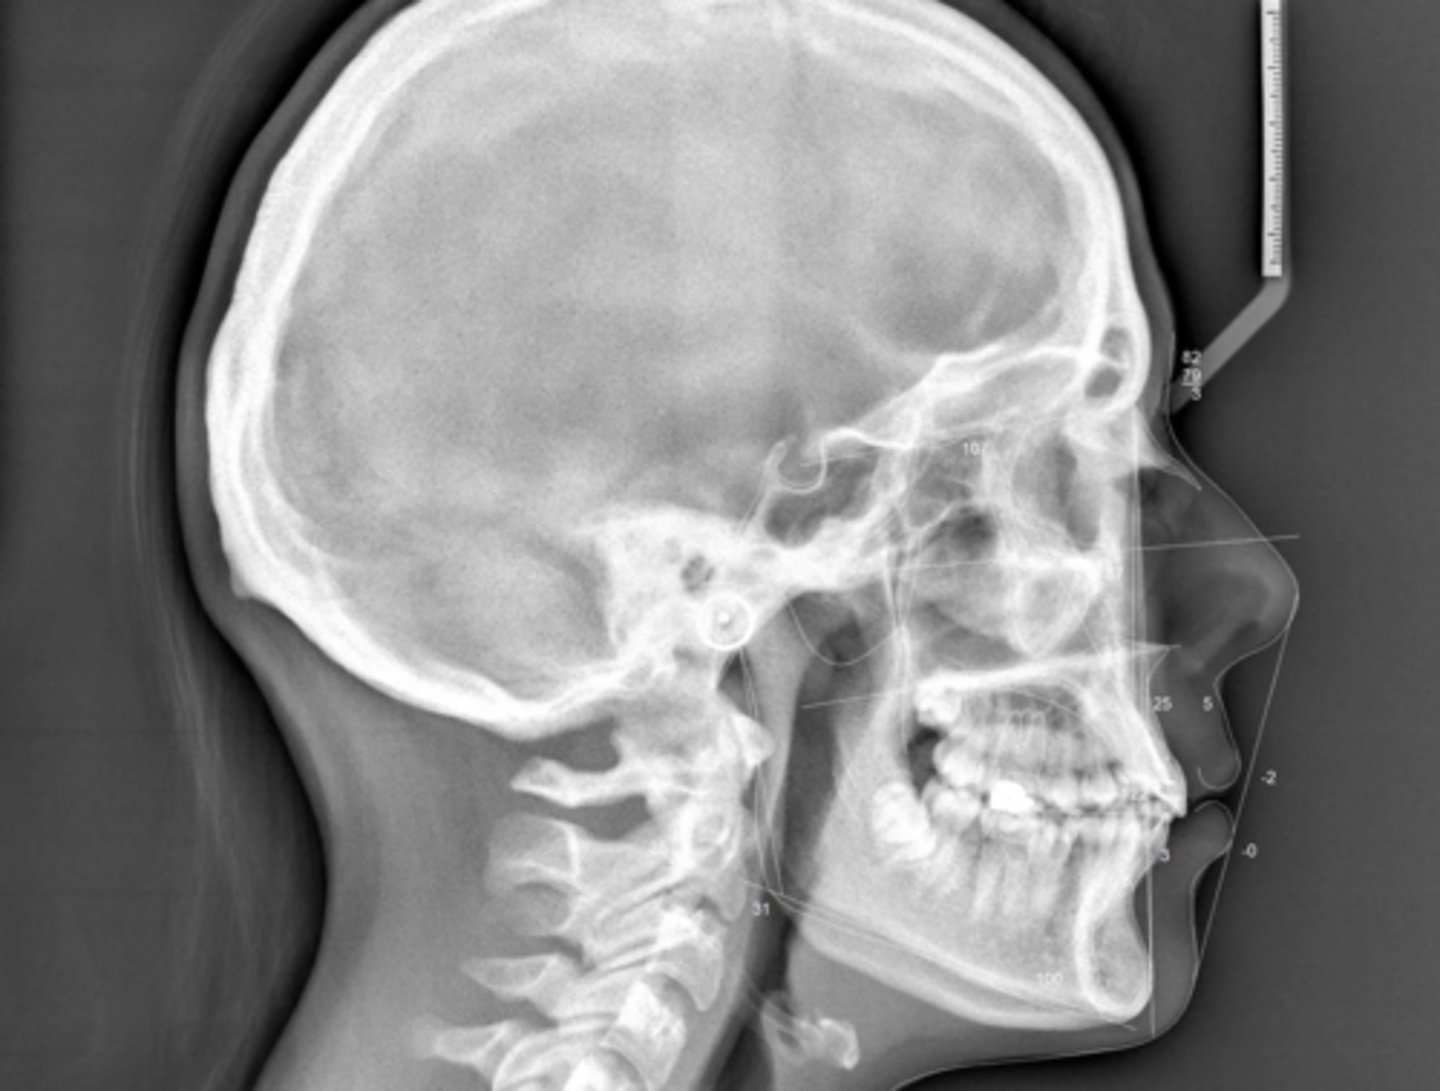

Class II skeletal (very light)

What type of skeletal malocclusion is this patient?

Hypodivergent

Are the hyper-, hypo-, o normo- divergent?

proclined

Maxillary incisors are?